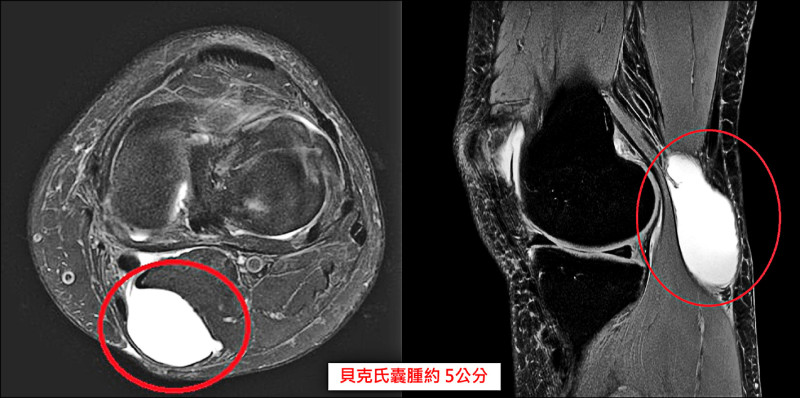

婦後膝窩長腫塊、蹲跪會麻 揪出「貝克氏囊腫」作怪